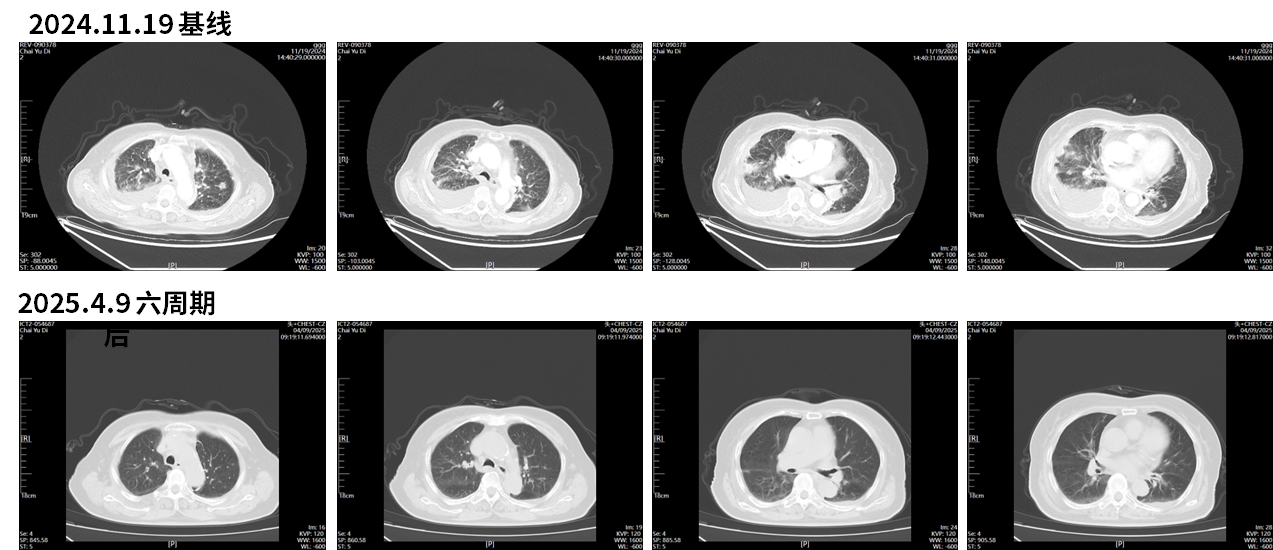

2024.11.19胸部CT示:左肺上叶恶性肿瘤可能,双肺、双侧胸膜发转移灶,纵隔内多发稍大淋巴结;双侧少量胸腔积液伴双肺下叶局限性肺不张;主动脉及冠状动脉钙化。

图1 2024.11.19 胸部CT结果